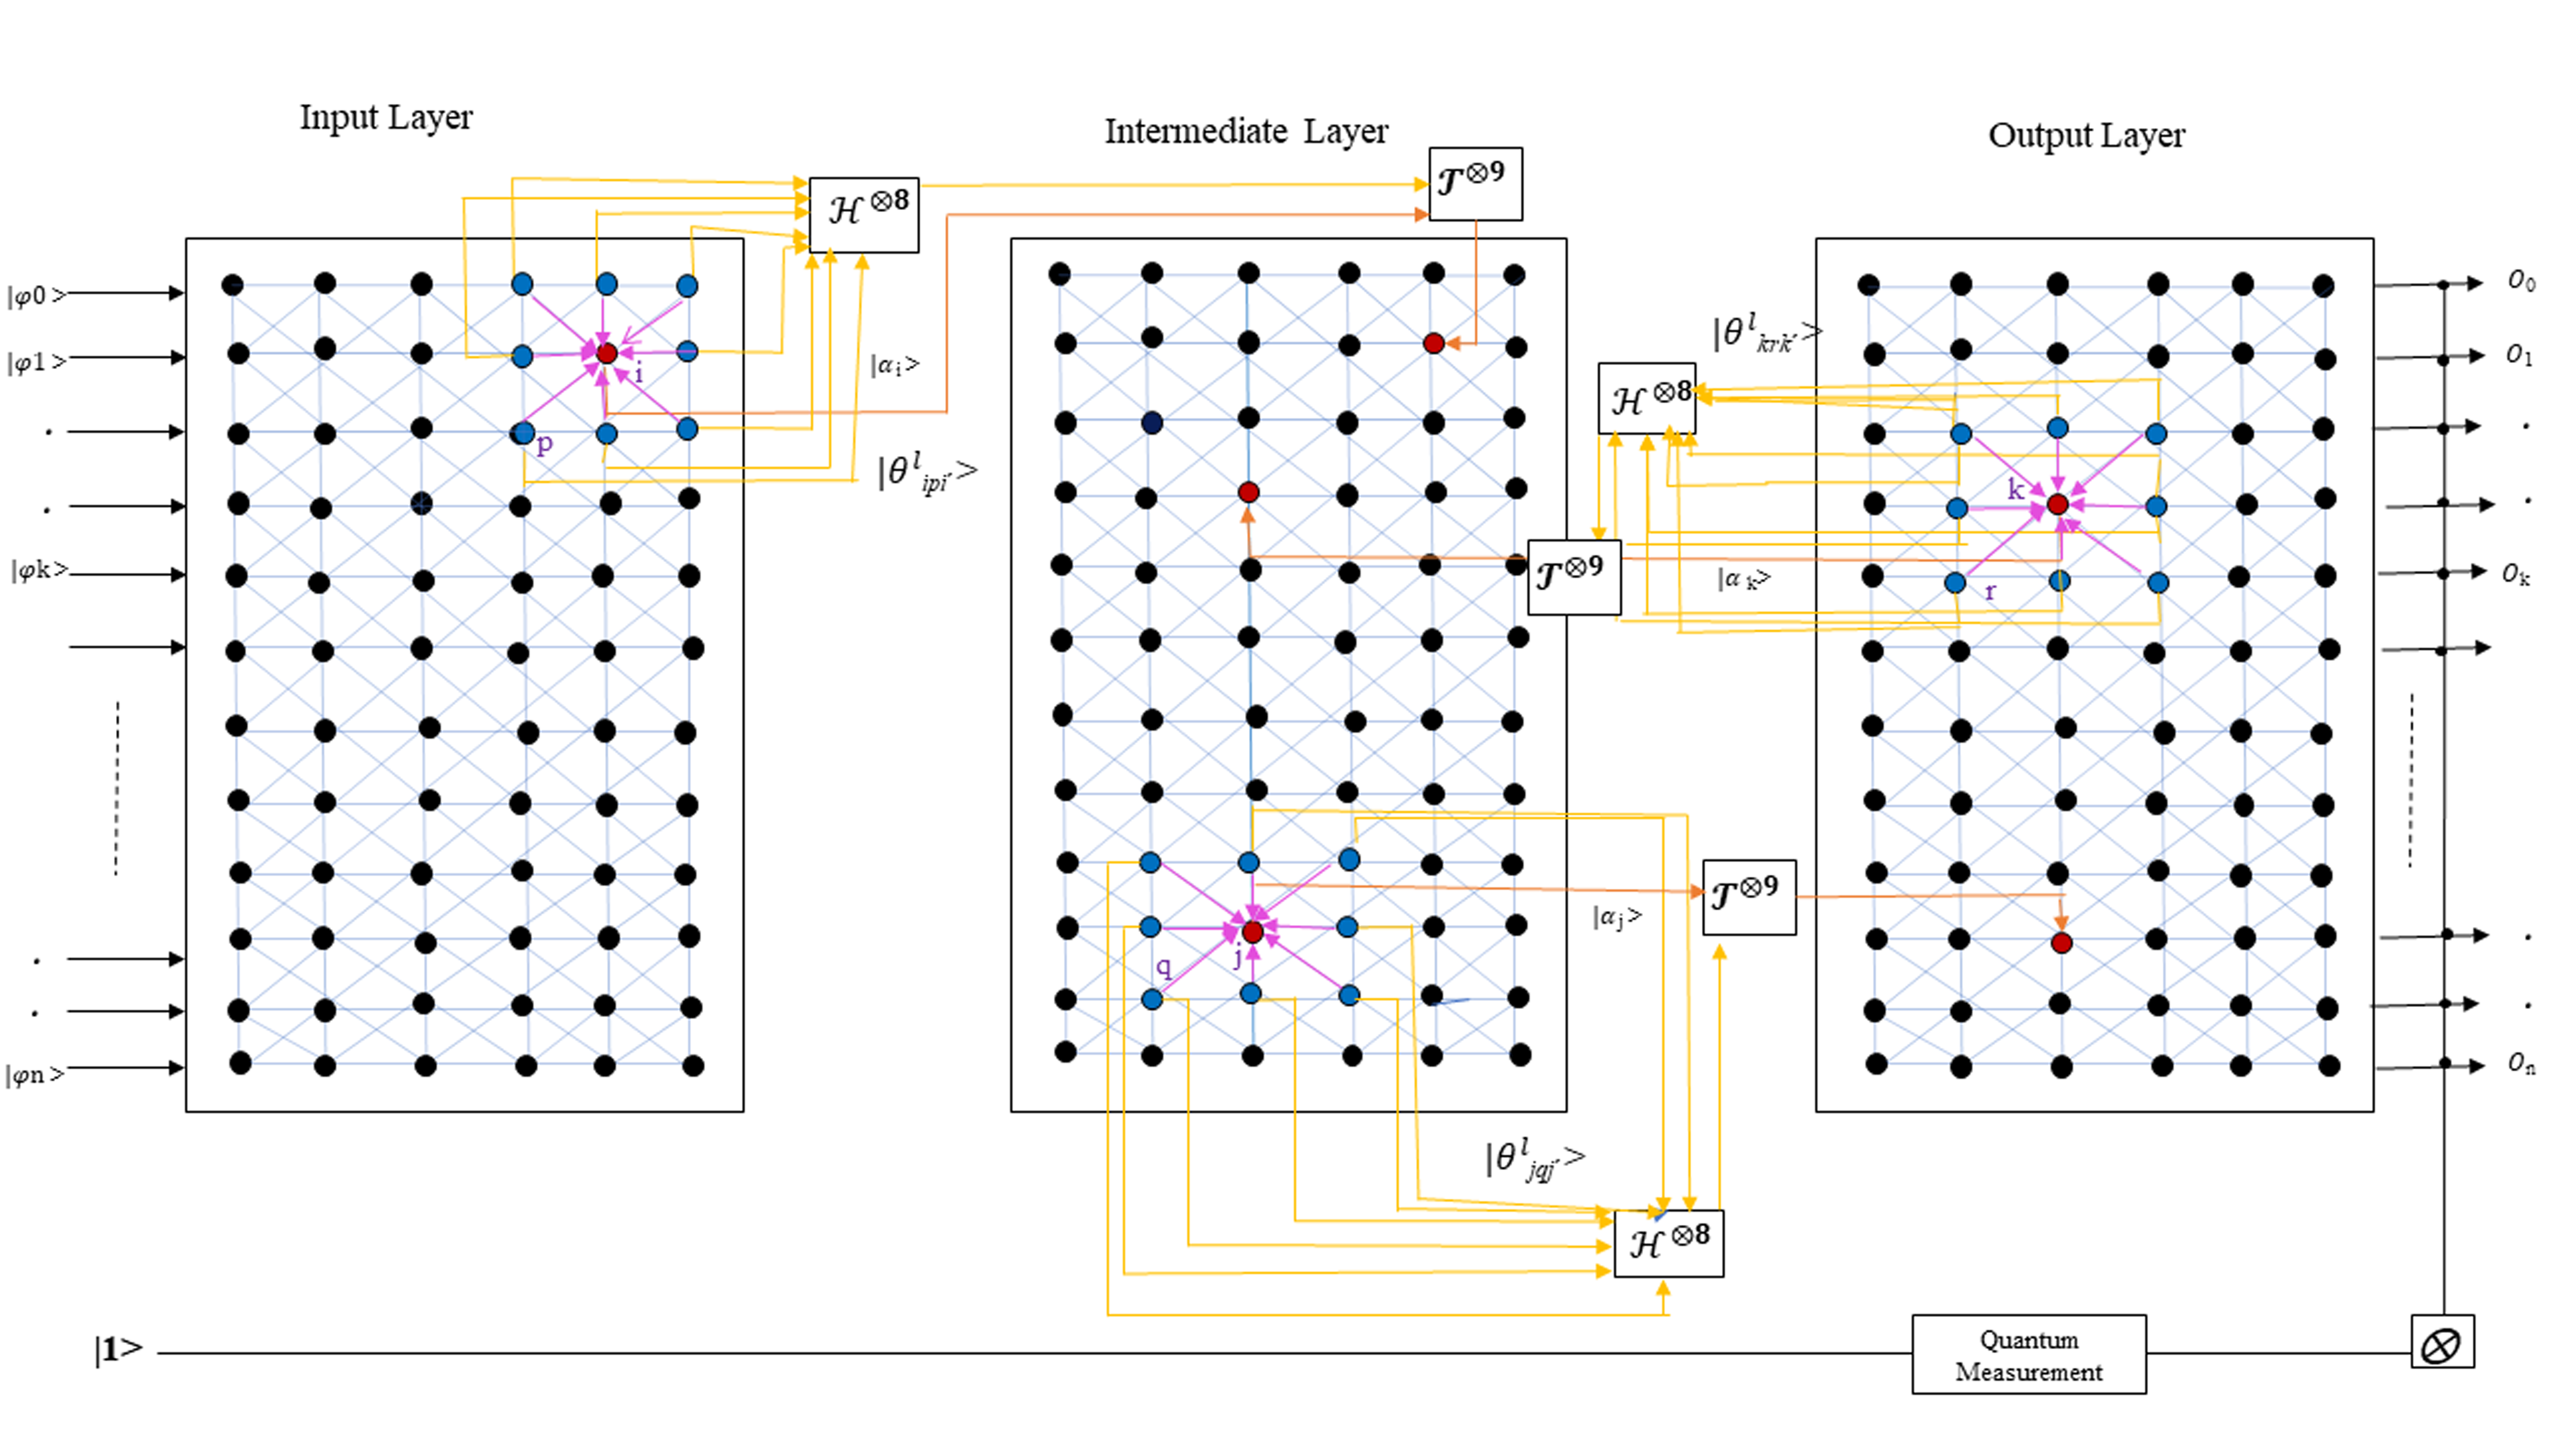

The suggested quantum fully self-supervised neural network architecture comprises trinity layers of qutrit neurons arranged as input, intermediate and output layers. A schematic outline of the QFS-Net architecture as a quantum neural network model is illustrated Figure 1.

The information processing unit of the QFS-Net architecture is depicted using quantum neurons (qutrits) reflected in the trinity layers using the combined matrix notation.

Hence, each quantum neuron constitutes a qutrit state designated as .

Each layer of the quantum self-supervised neural network architecture is organized by combining the qutrit neurons in a fully-connected fashion with intra-connection strength as (qutrit state). The main characteristic of the network architecture lies in the organization of the 8-connected second-order neighborhood subsets of each quantum neuron in the layers of the underlying architecture and propagation to the subsequent layers for further processing. The input, intermediate/hidden and output layers are inter-connected through self-forward propagation of the qutrit states in the 8-connected neighborhood fashion. On the contrary, the inter-connections are established from the output layer to intermediate layer entailing self-counter-propagation obviating the quantum back-propagation algorithm and thereby reducing time complexity. Finally, a quantum observation process allows the qutrit states to collapse to one of the basis states ( or as is considered as a temporary state). We obtain true outcome at the output layer of the QFS-Net once the network converges, else quantum states undergo further processing.

V-A Qutrit-inspired Fully Self-supervised Quantum Neural Network Model

The novel quantum fully self-supervised neural network model based on qutrits adopts twofold schemes. The qutrit neurons of each layer are realized using a transformation gate (realization mapping) and the inter-connection weights are mapped using the phase Hadamard gates () applicable on qutrits. The angle of rotation is set as relative difference of quantum information (marked by pink arrow in Figure 1) between each candidate qutrit neuron and the neighborhood qutrit neuron of the same layer employed in the rotation gate for updating the inter-layer interconnections. The rotation angle for the inter-connection weights and the threshold are set as and , respectively. The inter-connection weights between the qutrit neurons (denoted as and ) of two adjacent layers are depicted as and measured as the relative difference between the candidate qutrit neuron and the 8-connected neighborhood quantum neuron . The realization of the network weights are mapped using the Hadamard gate () inspired by the proposed QNNM model by suppressing the highest basic level () of qutrit as a temporary storage as